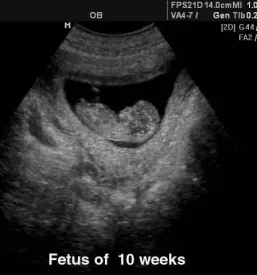

V naši ambulanti se predvsem trudimo, da bi imeli čimbolj profesionalen, diskreten in strokoven pristop k problematiki, ki jo obravnavamo. Da pa bi našim pacientkam zagotovili le najboljše, se nenehno izobražujemo in skušamo dosledno slediti sodobnim smernicam, ki se izoblikujejo tako pri nas kot tudi v tujini. Zato je med drugim na voljo tudi 3d 4D UZ - oziroma ultrazvočni pregled ploda.

V sklopu svoje ambulante ponujamo ginekološko in porodniško dejavnost, poleg tega svojim pacientkam nudimo preglede dojk in različne oblike ultrazvoka. Samoplačniško izdelamo tudi 3D 4D UZ.